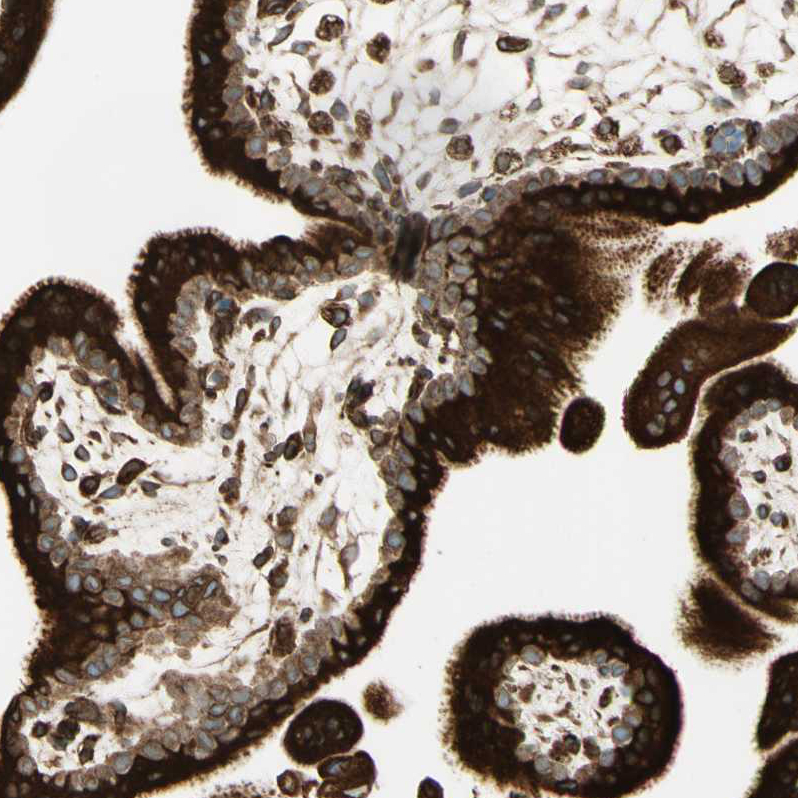

Immunohistochemical staining of human cerebral cortex, placenta, testis and tonsil using Anti-CANX antibody HPA009433 (A) shows similar protein distribution across tissues to independent antibody HPA009696 (B).